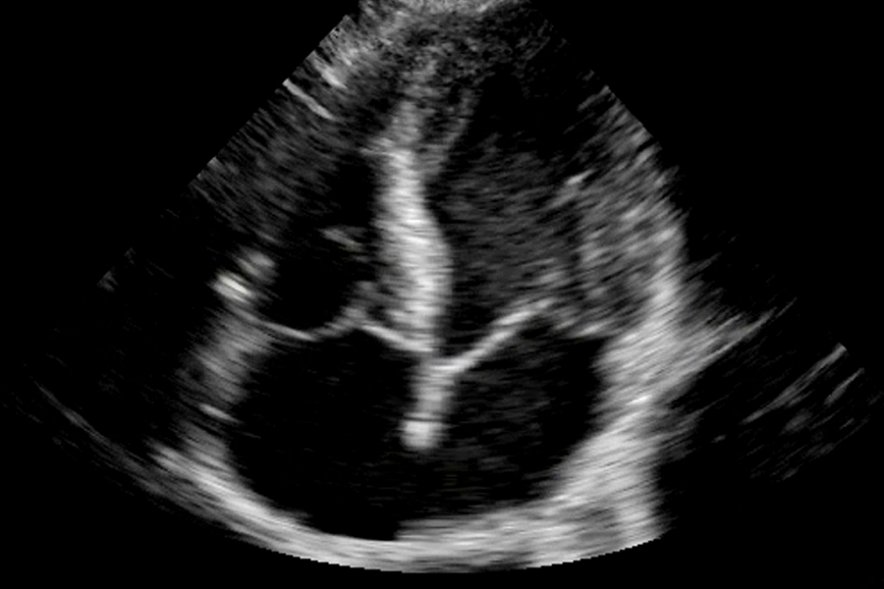

Новая технология, разработанная специалистами компании General Electric, позволит получать объемные изображения внутренних органов в режиме реального времени. В отличие от использованных ранее методик, картина воссоздается не послойно – органы сразу изображаются трехмерными, благодаря чему в процессе исследования можно наблюдать за их движением.

Технология уже внедрена на практике: она используется для диагностики сердечно-сосудистой системы и напоминает УЗИ, которое делается во время беременности. Однако в алгоритмах обработки изображения в 3D-УЗИ и инновационном 4D-УЗИ имеются существенные различия. Так, будущим родителям достаточно увидеть гладкую кожу младенца; кардиологи же и другие специалисты стремятся разглядеть на экране мельчайшие неровности тканей, поэтому в cSound полученные изображения штрихуются по-другому.

Инновация позволяет рассмотреть даже такие детали, как влияние на кровоток тромбов в артериях, а также максимально точно представить, как работает сердечно-сосудистая система, если в функционировании сердечного клапана наблюдаются проблемы. Так как в процессе диагностики организм не подвергается воздействию радиоактивного излучения, ограничений частоты и продолжительности его использования практически нет.